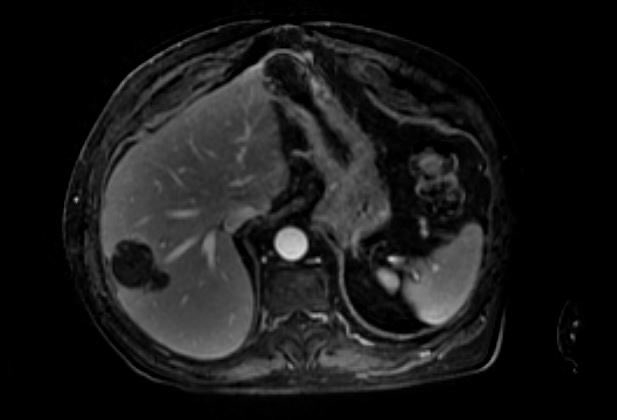

Case 124: with @BhaveshPopat7 @DrAntariksh Dr Vaibhav T . Beauty of conventional Lipiodol TACE - for a single well defined LR-5 lesion . #irad #MedTwitter #meded #medx @_backtable @SIRspecialists @SIRRFS @SIR_ECS